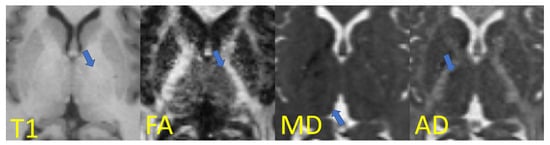

As mentioned previously, the vast majority of thalamus-segmentation methods use exclusively T1-weighted images [6,15,16,17,18,19,20,29], an MR sequence that fails to present a good contrast on the thalamus borders (Figure 3-T1). In contrast, diffusion MRI naturally accounts for the different properties of the brain’s microstructure [28,30,31,32,33], leading to higher contrast for certain sub-cortical structures, and consequently greater potential as a tool for segmentation problems.

Figure 3.

Axial slices in the thalamus region with thalamic borders highlighted (areas pointed by the arrows): T1-weighted image and examples of diffusion indices (fractional anisotropy, mean diffusivity, and axial diffusivity) from diffusion tensor imaging. Adapted with permission from Ref. [26]. 2021 Society of Photo-Optical Instrumentation Engineers (SPIE).

For example, when visualizing scalar maps computed from diffusion tensor imaging (Figure 3), the frontiers of the thalamus with other structures are clearly visible: on FA maps, for instance, the boundary between the thalamus and internal capsule is shown with a higher contrast due to the differing anisotropic diffusivity of these structures.